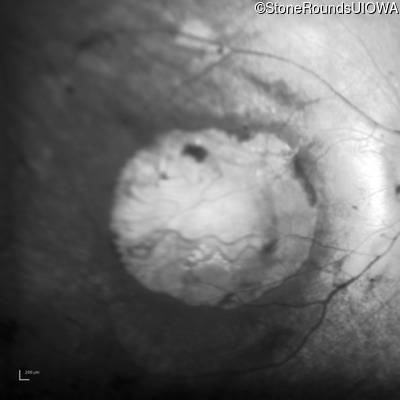

This 15 year old male had a macular abnormality noted two weeks ago when he was refracted for his first pair of glasses. Bone spicule-like pigmentation was first noticed a year later (age 16) during a routine follow-up eye exam.

Age at visit: 16 years

Age at visit: 18 years